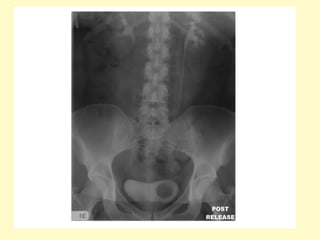

Prune-belly syndrome, IVU (a) and VCUG (b) images show the characteristic

large floppy bladder (★) and marked bilateral hydronephrosis and

hydroureter (u) with renal parenchymal wasting, note the anomalies in the

pelvic bones and both femurs due to renal osteodystrophy in b